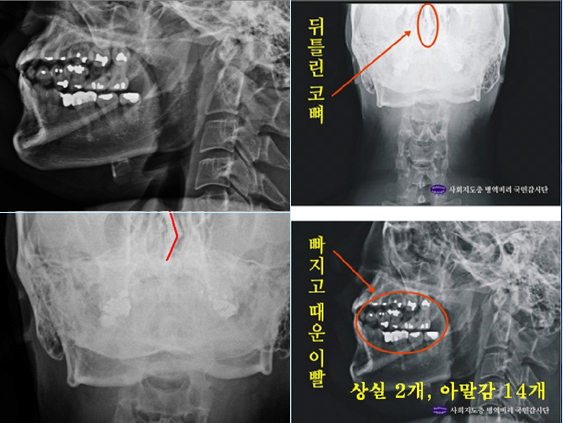

박주신 치과진료기록이 던지는 의문들박주신씨의 치과진료기록도 풀리지 않는 미스터리로 남아있다. 양승오 박사 등에 대한 검찰의 수사가 진행되던 지난해, 이 사건 피고인들은 박주신씨의 치아가 보이는 구외 X-Ray(이하 치아 X-Ray)를 근거로, 박주신씨의 신체를 촬영했다는 X-Ray 속 피사체가 제3의 인물일 가능성을 주장했다.

피고인들이 치아 X-Ray를 근거로, '피사체 바꿔치기' 의혹을 강하게 제기한 이유는, X-Ray에 나타난 치아의 상태가, 도저히 20대 중반 청년의 것이라고는 보기 힘든 특징을 갖고 있었기 때문이다.

주신씨 구외 X-Ray 사진을 보면, 치아 상태가 매우 불량하다는 사실을 알 수 있다. 치아 2개는 아예 없고, 아말감으로 때운 치아가 무려 14개에 달한다.

수은증기 방출 논란으로 문제가 되고 있는 아말감(Amalgam) 치료는 여러 가지 단점을 갖고 있어 사용빈도가 크게 줄고 있다는 것이 치과의료계의 공통된 평가다.

서울 방배동에 사는 중산층 청년이, 치과의사는 물론 환자들도 기피하는 아말감을 이용한 치과 치료를 이처럼 많이 받았다는 것은, 쉽게 받아들이기 어렵다는 것이 이들의 지적이다.

더욱 의심이 가는 부분은 주신씨의 경우, 하악 좌측 1소구치(아래쪽 좌측 첫 번째 작은 어금니)까지 아말감으로 치료했다는 사실이다.

그러나 이런 경우는 매우 드물다는 것이 치과의사들의 일반적인 견해다.

이 사건 피고인 중 한명인 치과의사 김우현씨는, 주신씨의 영구치가 맹출을 시작했을 것으로 추정되는 1990년대 중반 이후, 젊은 사람이 1소구치들을 포함한 구치부 치아 전체를 아말감으로 치료했다고 보기엔 무리가 있다고 지적했다.

치의학 박사 C씨는 뉴데일리와 기자와의 인터뷰에서 “주신씨의 전체적인 치료 상태를 보면, 소위 말하는 야매로 했을 가능성이 높다”고 밝혔다.

“(주신씨의 것이라고 알려진 구외 X-Ray 사진을 보면) 최근 국내에서 교육받은 치과의사의 치료라고 생각할 수 없을 정도”

“(주신씨 구외 X-Ray 사진 상의) 45번, 46번 보철치료 및 치아 상실 문제도 마찬가지다. 보철물로는 상당히 저렴한 비귀금속 합금을 사용한 것으로 보인다. 37번 치아는 아예 없는 상태로 방치하기도 했다”

“박주신씨의 가정환경을 고려하면, 이런 치료를 받았을 가능성은 1%도 안 된다. 서울 방배동에 거주했던 중산층 이상의 가정에서는 흔치 않은 상황”

주신씨의 치아 아말감 치료와 관련돼, 김우현씨는 “혹자는 아말감 치료를 10개 이상 한 게 무슨 대수냐? 하면서 무시하는 경향이 있지만, 이는 모든 인과관계와 사실들을 무시하려는 것”이라고 비판했다.주신씨의 구외 X-Ray는 그가 허리 MRI를 촬영하면서 같이 찍은 X-Ray 사진들 중에서 치아가 보이는 X-Ray 사진이다.

따라서 구외 X-Ray 상에 나타나는 각종 의혹은, 허리 MRI와 더불어 해당 피사체가 주신씨가 아닐 가능성에 무게를 더한다.

주신씨의 구외 X-Ray 사진 상에 나타나는 의문들은, 양승오 박사 등이 주신씨의 병역비리 의혹을 제기하게 된 핵심 요인 중 하나였다.

치아의 치료상태는 매우 불량하고, 심지어 골반 X-Ray 사진에서는 골절된 뼈조각까지 발견됐다.주신씨의 것으로 알려진 치아 X-Ray 사진을 본 치의학 박사 C씨의 소견이다

“자료를 보면 2개의 이빨은 아예 없고, 아말감으로 때운 치아 14개가 보인다.

게다가 환자는 하악 1소구치(아래 어금니 앞쪽)까지 아말감으로 치료했다.

(젊은 사람이) 이런 경우는 매우 드물다.”“특히 전체적인 치료 상태를 보면, 소위 말하는 [야매]로 했을 가능성이 높다.

최근 국내에서 교육받은 치과의사의 치료라고 생각할 수 없을 정도다.

45번, 46번 보철 치료 및 치아 상실 문제에 있어서도 마찬가지다.

보철물로는 상당히 저렴한 비귀금속 합금을 사용한 것으로 보인다.

37번 치아는 아예 없는 상태로 방치하기도 했다.”“박주신의 가정환경을 고려하면, 이런 치료를 받았을 가능성은 1%도 안 된다.

서울 방배동에 거주했던 중산층 이상의 가정에서는 흔치 않은 상황이다.”